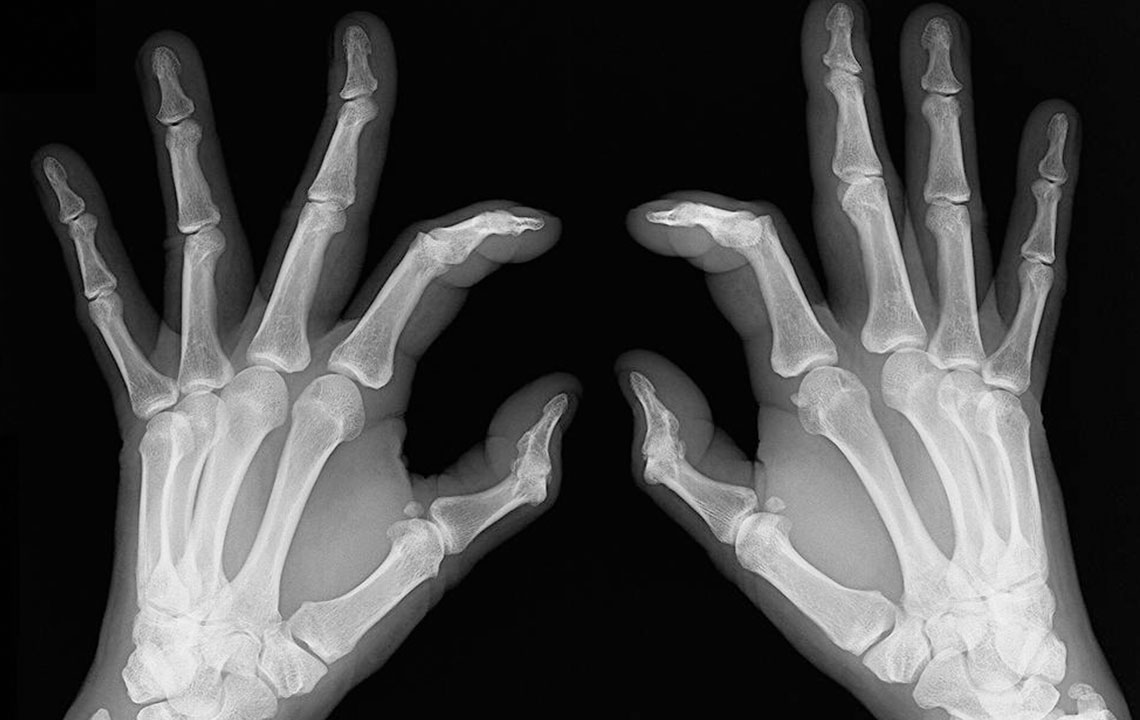

Early signs of rheumatoid arthritis and how to catch them

People who have rheumatoid arthritis often wake-up early in the morning complaining of stiff joints and restricted movement. The mobility is back slowly and with little joint movements . Joint redness: Sometimes the troubled area also experiences redness and feels warm to the touch. However, make sure the redness is not due to reasons such as a bruise or a scrape of the skin. Bone deformation: Arthritis also attacks the bones and makes them crooked and stiff. Look out for signs of any subtle changes in your joints and test them for pain levels.